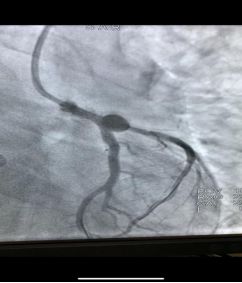

不看不知道,一看真的吓一跳,这下终于找到了患者顽固性低血压的原因。造影结果显示患者左冠脉堵塞严重,需立即放支架,否则随时可能再次发生心跳骤停,而且一旦发生,几乎不可逆转。放支架技术难度相当大,手术台上死亡率高达20%。心血管内科一病区副主任陈玺全明确向家属交代了患者目前的情况以及手术存在的风险,表明该技术在医院已十分成熟,一定会竭尽全力。在征得家属同意后,陈玺全副主任带领手术团队,经过40多分钟的努力,成功为患者实行了心脏支架植入手术。